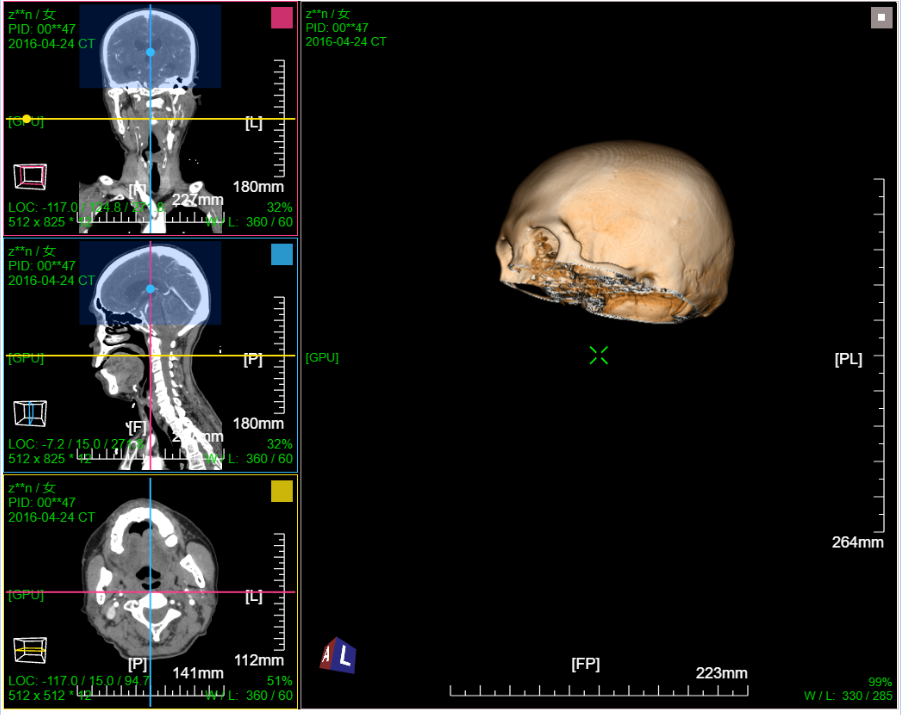

八、三维浏览功能操作和截图

左键双击MPR窗口可在MPR三窗口和1x1窗口间切换;三维渲染窗口左键双击在在1x1视图模式和当前视图模式切换

点击MPR窗口右上角颜色块可AXIS轴位、CORO冠位、SAGI矢位切片切换

VR容积渲染;鼠标右键默认实时调整当前VR传输函数

VR渲染一键去头骨:首先进行体包围盒裁剪选择头颅部分限制区域生长范围,然后点击一键去头骨功能